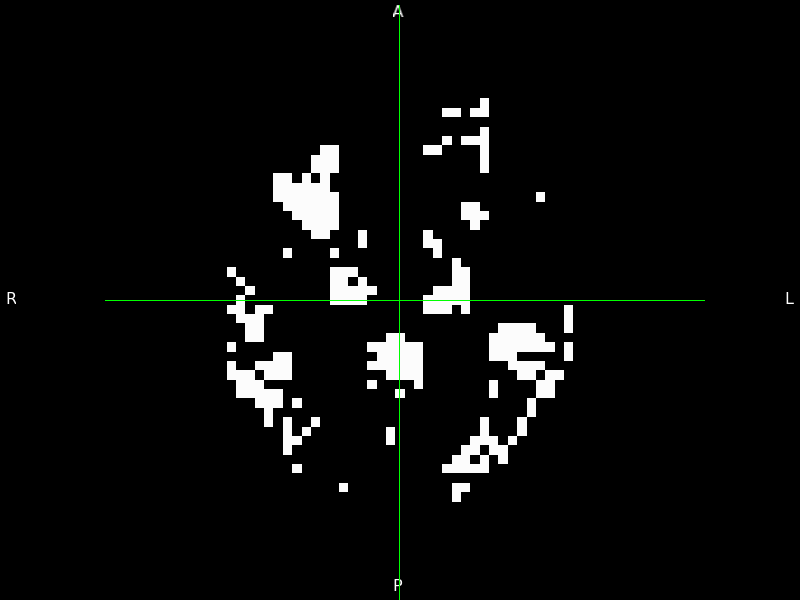

3.4.1 Pixel-level disease progression events in AMD

We apply the vEBM to OCT data from the DU cohort to reveal the first pixel-level sequence of disease events in AMD (Figure 6). The density of RPEDC spread around the centre of the eye reflects previous observations [62], and the vEBM provides a much finer-detailed progression pattern.

Refer to caption

Figure 6: Pixel-level disease progression sequence in AMD obtained by the vEBM. White pixels correspond to events that have occurred; black not yet occurred. We have selected 10 sequence positions at uniform steps of 50 across the total of 537 in the full sequence, with the top left figure corresponding to position 80 and the bottom right to position 530. Images were made from the vEBM output using 3D Slicer (https://www.slicer.org/).